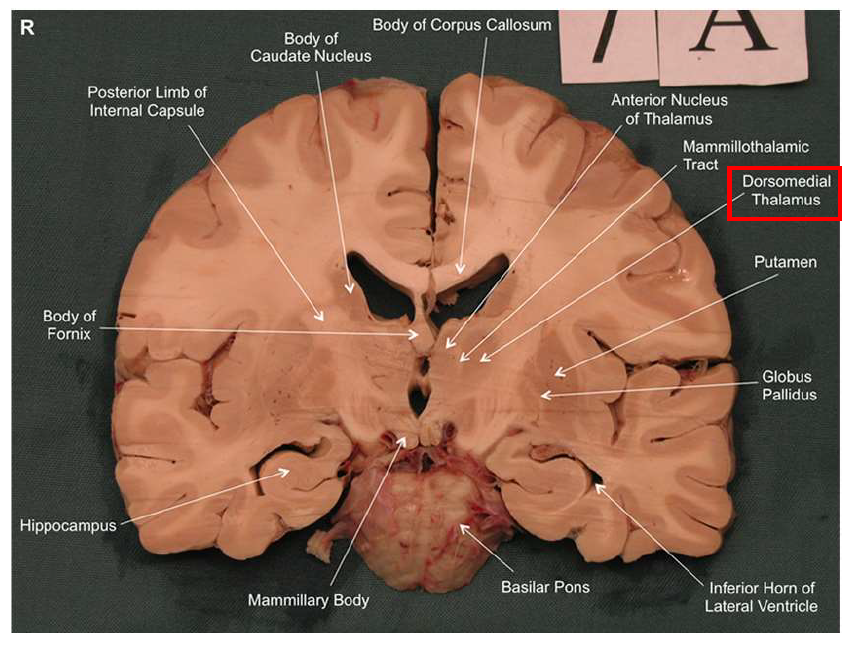

What is the fornix of the hippocampus?

Hippocampus output pathway (C-shaped)

Connects hippocampus to hypothalamus/mamillary bodies

Carries information to and from hippocampus

Important for memory consolidation and retrieval

What is this?

hippocampal fornix

How does the hippocampus form memories?

Association areas activate the hippocampus, which reverberates in the Papez circuit until information is stored permanently

Hippocampus → fornix → mamillary bodies → anterior thalamic nucleus → cingulate cortex → hypothalamus